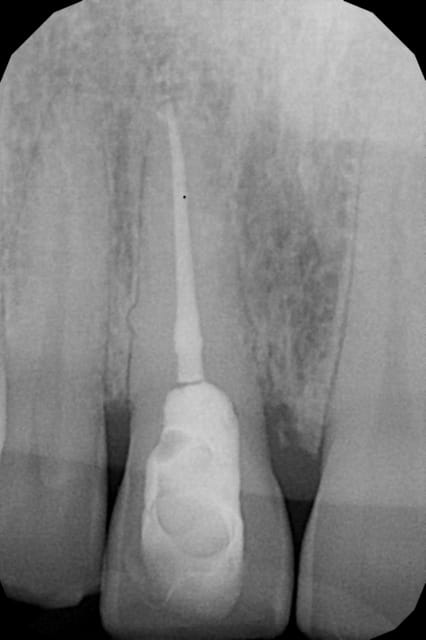

J'ai fait une nouvelle radio sous un angle un peu différent, la 1ère a été faite avec angulateur. Je lui ai presris un scan et je vous tiendrai au courant.

grossemolaire

12/04/2016 à 16h44

Bin voila, effectivement fracture. Je ne voyais rien au scan mais elle est devenu mobile avec une fistule.